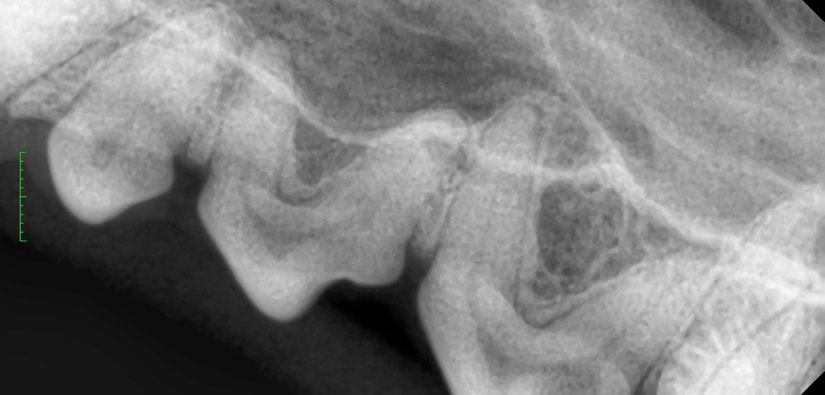

歯のX線撮影を行います。

X線写真で歯周病の程度を判断します。

歯科処置は処置室のシンクの上で歯科・外傷処置用の麻酔器を使用して行います。まず、コーンビームCT装置と歯科用X線撮影装置を用いて歯と骨の状態を評価し、歯周病の程度を判断します。合わせて歯の動揺がないか、歯肉ポケット内の状態がどうかを調べていき、抜歯の必要があるかを判断します。超音波スケーラーで歯石を落としていきます(スケーリング)。この時、歯の熱損傷を防ぐために水しぶきが飛びますので顔の他の部位が濡れて体温が下がらないように配慮します。歯肉ポケット内の歯垢や歯石をキュレットで除去し、不正な肉芽を除去します。抜歯が必要であれば必要に応じてマイクロエンジンを使って歯を切断・分割して抜歯します。